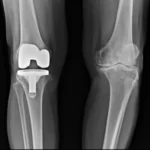

Infektion der Knochen und Gelenke durch Staphylokokken Gold.

Geheilt von einer Staphylokokkeninfektion an einer Knieprothese durch Phagentherapie.

Als ich vor zwei Monaten meinen Chirurgen wieder aufsuchte, um ihm mitzuteilen, dass ich vorerst nicht erneut operiert werden wollte, bestätigte er mir auf Grundlage meiner guten Analysen und Röntgenbilder, dass dies nicht notwendig sei. Wir würden in 6 Monaten erneut schauen. Aber er stellte mir keine Fragen zu den Phagen… Es hat mir gut getan, nicht auf sie gehört zu haben und die besagte Phagentherapie zu machen. Danke, Georgien! Danke, Phagen! Danke, PHAGETHERAPYGEORGIA.EU!Thierry De Passemar

Lire plus “Geheilt von einer Staphylokokkeninfektion an einer Knieprothese durch Phagentherapie.”